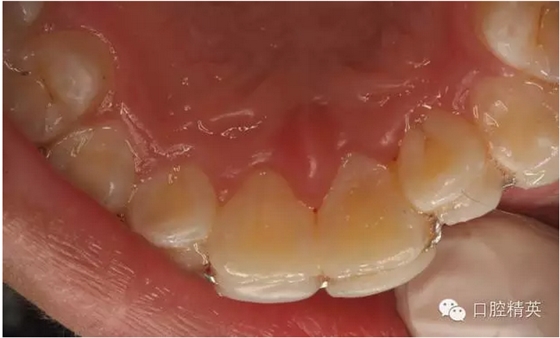

圖7.腭側(cè)口內(nèi)像,齦乳頭水腫消失

圖13.拋光完畢的牙面,齦乳頭色澤正常,無(wú)牙周袋。21不松動(dòng)